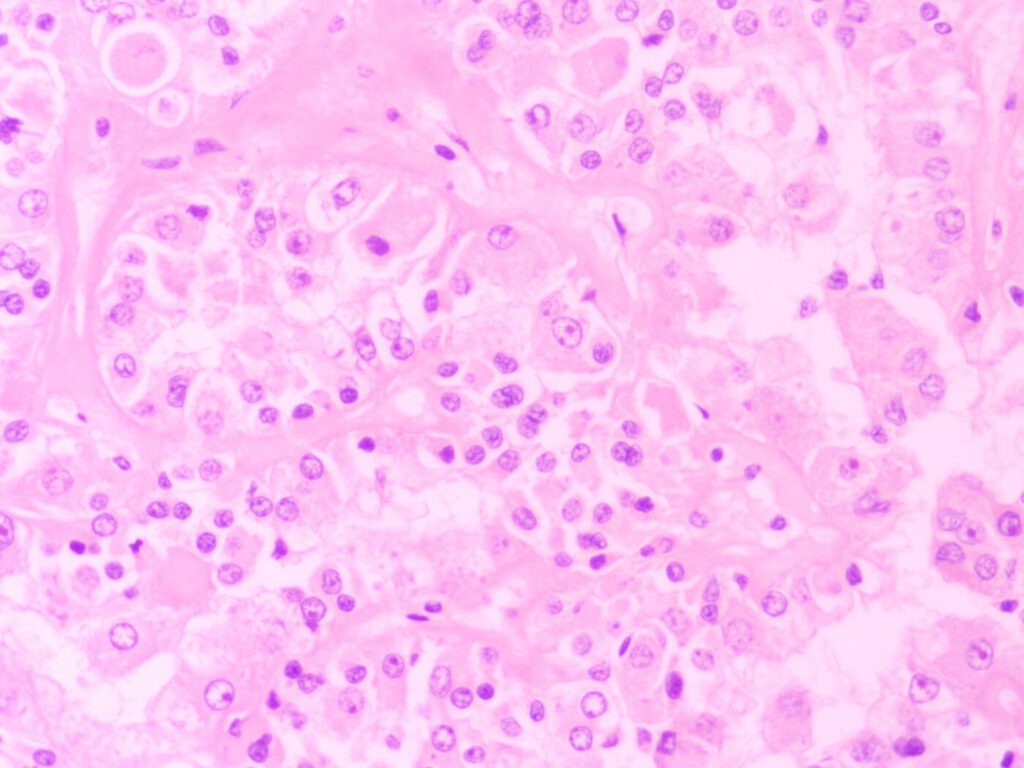

The representative sections (or some small specimens in entirety) are then put in small cassettes and put through a series of processing steps. Ultra-thin slices of the tissue are then cut and put on glass slides. The tissue is stained and is then examined by pathologists to give a diagnosis.

Special histological procedures available include various special stains and immunohistochemistry (IHC) to further aid or refine diagnosis.